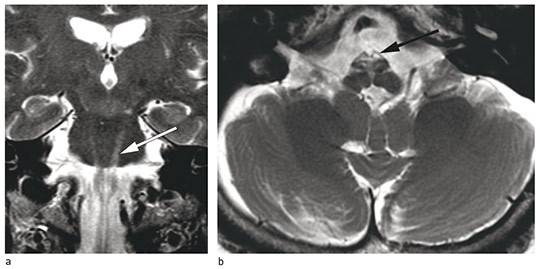

Symmetrical signal abnormalities and atrophy were noted in the ventral medulla oblongata, corresponding to the pyramidal tract. The signal abnormalities extended upwards into the pons equally on both sides, although the mesencephalon was spared, and down the spinal cord to mid thoracic level. Symmetrical hyperintensities were additionally seen in the dentate nucleus of the cerebellum on T2-weighted images (Fig. 1).

Figure 1 MRI of the patient’s brain at 70 years of age. T2-weighted images. Abnormalities are asymmetrical and most pronounced on the left, which is consistent with the patient's right-dominant clinical signs. a) Coronal plane shows hyperintensities along the pyramidal tracts in the pons (white arrow). b) Axial plane shows hyperintensities in the medulla oblongata (black arrow)